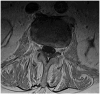

West Nile virus infection poses a significant threat, especially during the warmer months when mosquitoes are abundant. Clinicians must remain vigilant for neuroinvasive illness in patients presenting with febrile symptoms and malaise following mosquito exposure. While magnetic resonance imaging and cerebrospinal fluid analysis aid in differential diagnosis, detecting West Nile immunoglobulin M in serum is crucial for definitive diagnosis. Treatment primarily involves supportive care due to the absence of established regimens, though promising outcomes have been reported with plasma exchange and intravenous immunoglobulin. We present the case of an 83-year-old resident of Alabama, an avid gardener living near a pond, who initially exhibited symptoms of productive cough, diarrhea, fever, and generalized malaise. However, within 48 h, he developed hypoxemia, functional quadriplegia, and bulbar palsy necessitating intubation. Diagnostic evaluations, including magnetic resonance imaging and positive West Nile virus immunoglobulin M in serum, confirmed West Nile virus-associated poliomyelitis viral syndrome, prompting intravenous immunoglobulin therapy. This case highlights the importance of promptly identifying and managing West Nile virus infection, especially in regions susceptible to mosquito-borne diseases, and being vigilant of the disease in non-endemic regions. The case also begs the question of the timing and efficacy of intravenous immunoglobulin and plasma exchange in West Nile virus infection and the fact that more data should be collected on these therapies.

Keywords: West Nile encephalitis; West Nile neuroinvasive disease with poliomyelitis syndrome; West Nile virus; caudal nerve root enhancement; flavivirus.